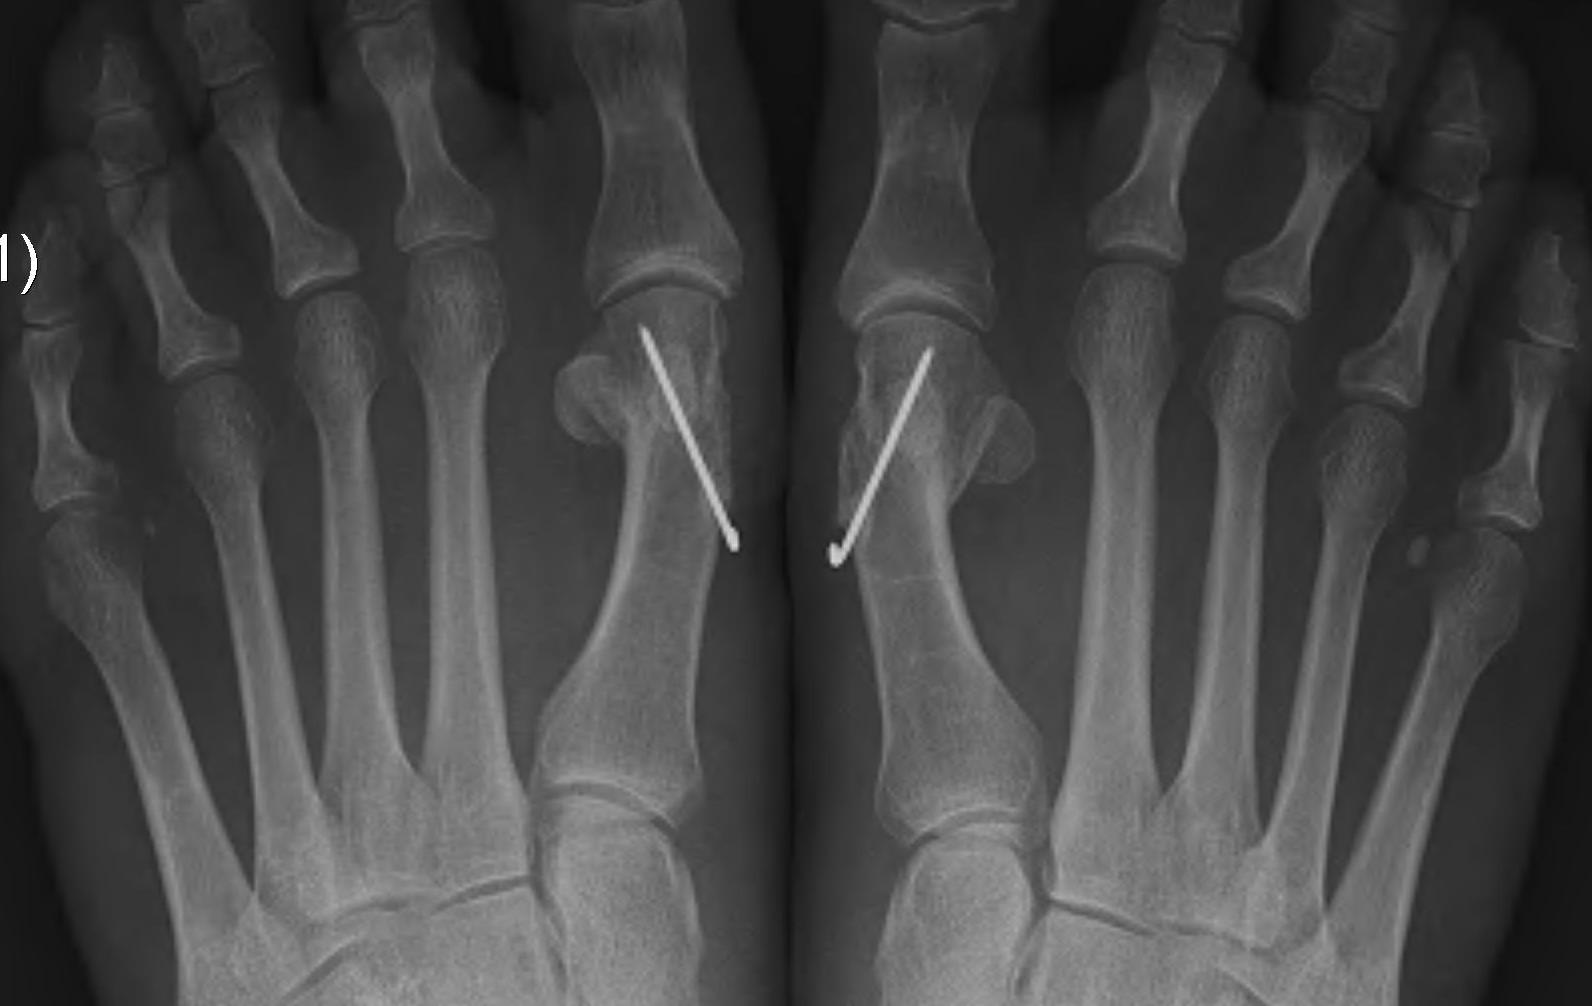

Akin osteotomy

Indications

- hallux interphalangeus > 10o

Technique

- medial closing wedge osteotomy of P1